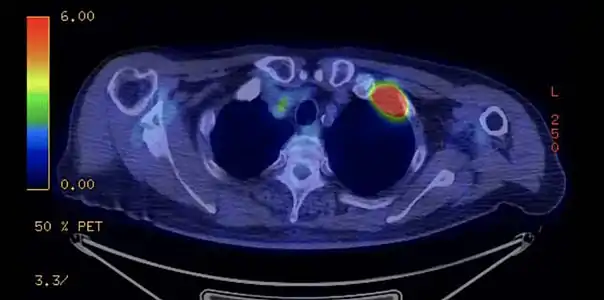

TDM d'une tumeur de Pancoast gauche envahissant l'arc antérieur de la 1re et de la 2e côte (flèche jaune). PET-scanner du même patient[14].

PET-scanner du même patient[14].

Dans le cadre du bilan d'extension, le TEP scanner aide à rechercher les localisations secondaires métastatiques et à préciser l'envahissement ganglionnaire.